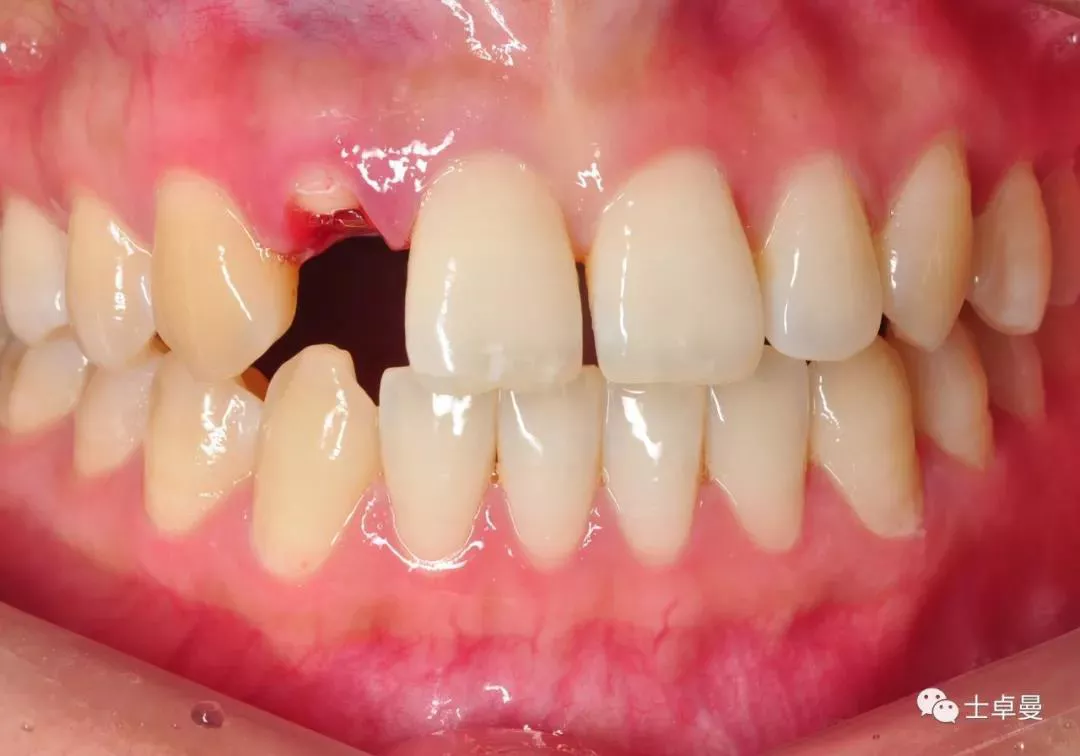

·       根尖穿孔区局部翻瓣,暴露穿孔部位;

根尖穿孔区翻瓣

·      放置骨粉、骨膜;

根尖区局部植骨

覆盖胶原膜

·       缝合;

缝合颌面观